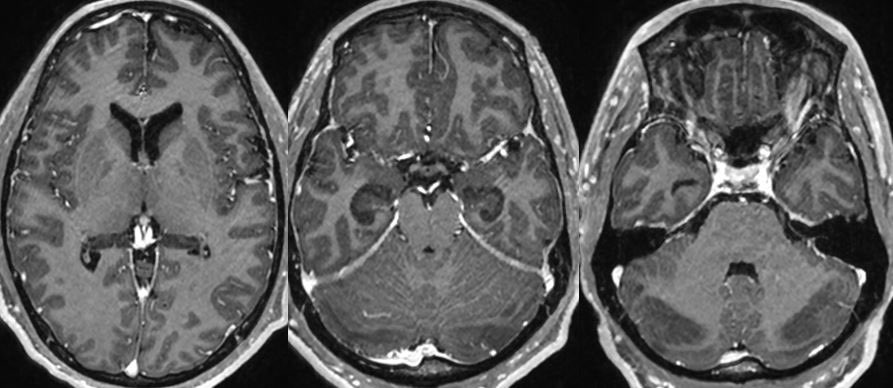

Psychiatry Excellence

Psychiatry Excellence@psycheureka·

Imaging Findings → White Matter Hyperintensities T2-weighted FLAIR MRI showed bilateral periventricular and deep white matter hyperintensities, consistent with small vessel ischaemic changes. These lesions are often linked to vascular depression and late-onset psychosis. Psych Scene Tip: In late-onset depression or new-onset psychosis, always consider cerebrovascular contributions.

A 59-year-old woman with no prior psychiatric history presented with severe depressive symptoms, nihilistic delusions, and poor insight. She required inpatient admission due to suicidality and functional decline. Let’s examine this case and its imaging to highlight the diagnostic and management considerations. 🧵👇